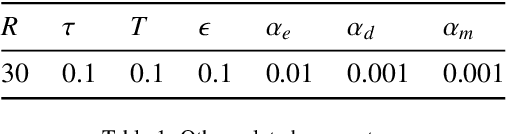

Multi-level colonoscopy malignant tissue detection with adversarial CAC-UNet

The automatic and objective medical diagnostic model can be valuable to achieve early cancer detection, and thus reducing the mortality rate. In this paper, we propose a highly efficient multi-level malignant tissue detection through the designed adversarial CAC-UNet. A patch-level model with a pre-prediction strategy and a malignancy area guided label smoothing is adopted to remove the negative WSIs, with which to lower the risk of false positive detection. For the selected key patches by multi-model ensemble, an adversarial context-aware and appearance consistency UNet (CAC-UNet) is designed to achieve robust segmentation. In CAC-UNet, mirror designed discriminators are able to seamlessly fuse the whole feature maps of the skillfully designed powerful backbone network without any information loss. Besides, a mask prior is further added to guide the accurate segmentation mask prediction through an extra mask-domain discriminator. The proposed scheme achieves the best results in MICCAI DigestPath2019 challenge on colonoscopy tissue segmentation and classification task. The full implementation details and the trained models are available at https://github.com/Raykoooo/CAC-UNet.